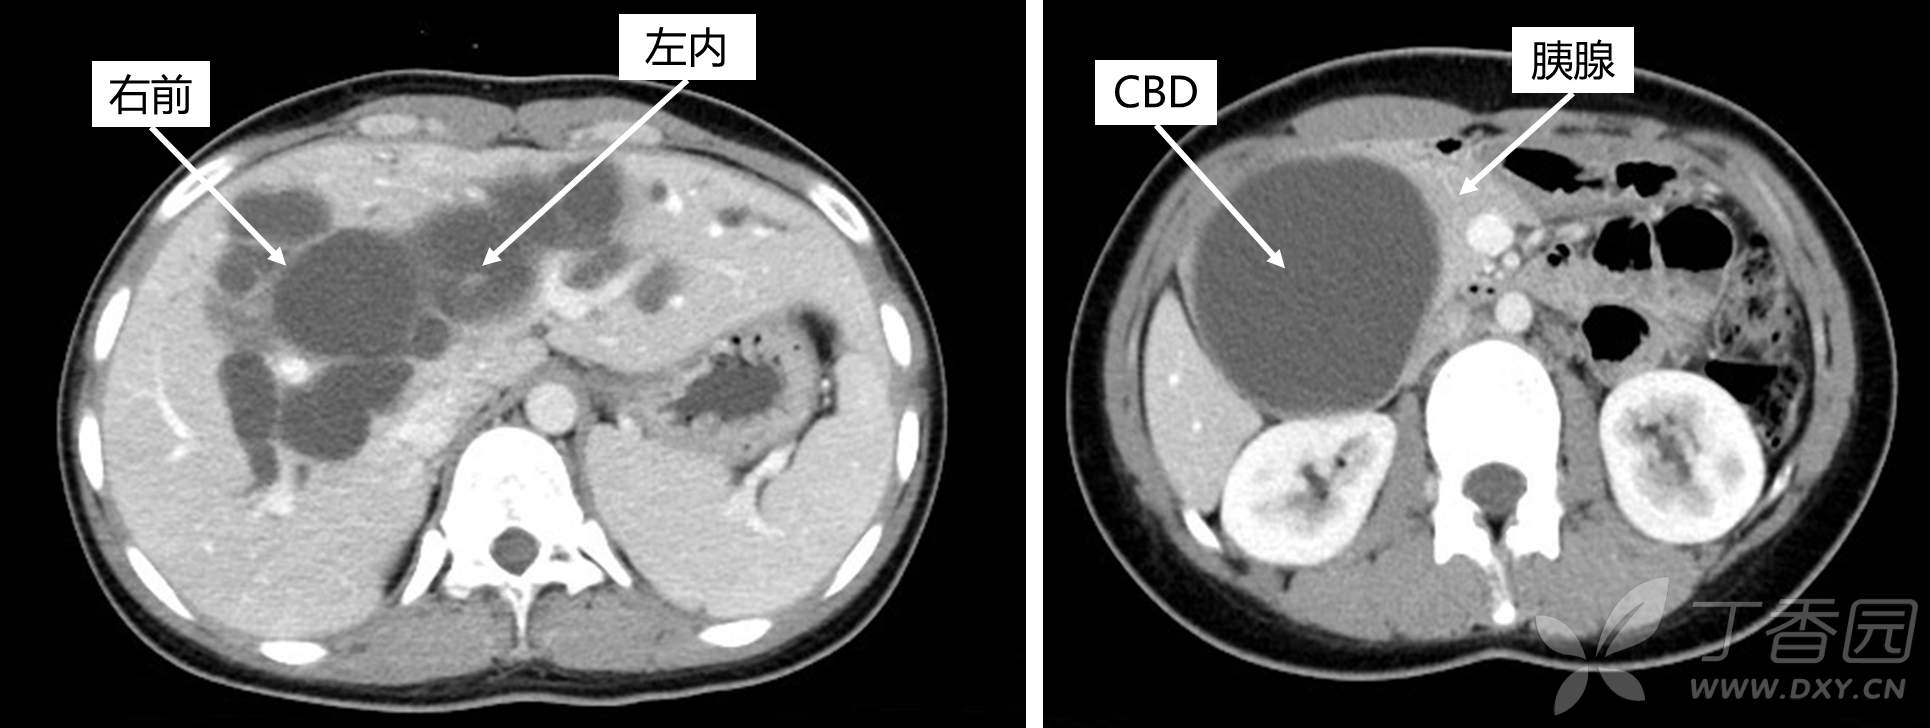

术前的仔细分析非常关键,这里的年轻医生都可以做的很好,如图标注:左内叶、右前叶的肝内胆管都扩张了,胆总管扩张严重一直达到胰腺实质内:

方案二中肝切除+胆肠吻合:剩余肝体积60%。虽然第二种手术难度大,但是最大程度的保留了剩余脏器功能,符合精准外科的理念。主刀L教授(肝胆外科不多见的美女专家)决定按第二种方案办,说到做到,如图: